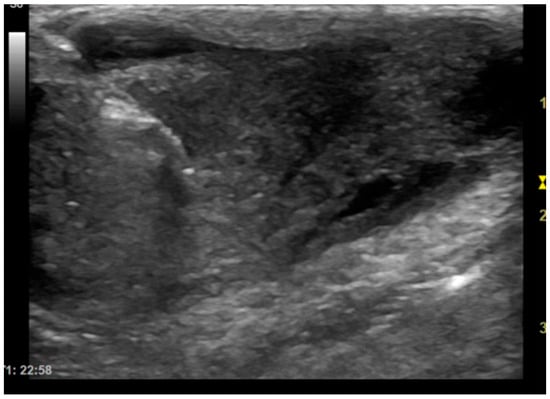

The patients included in the study underwent imaging-guided biopsies, specifically under US or CT guidance, of the masses under examination as shown in Figure 1 and Figure 2. Biopsy samples were collected using a semi-automatic spring-loaded tru-cut (14 G) in the case of soft tissue lesions and a bone needle (8–10 G) for bone tissue. These interventional diagnostic methods were performed after monitoring and anesthetizing the patient, under the continuous supervision of the anesthetist in charge. Trichotomy of the area of interest was performed, followed by surgical scrubbing with betadine and alcohol. Once the patient was prepared, a small incision was made with a number 11 scalpel blade on the skin surface, through which the tru-cut (14 G) or bone needle (8–10 G) was subsequently inserted. The biopsies were performed using ultrasound guidance or computed tomography, depending on the case, the location of the lesion and the availability of instruments.

Figure 1. Dog, Mixed breed, 5 y, neutered male. Percutaneous ultrasound-guided biopsy of a subcutaneous mass. Final diagnosis: pyogranuloma.